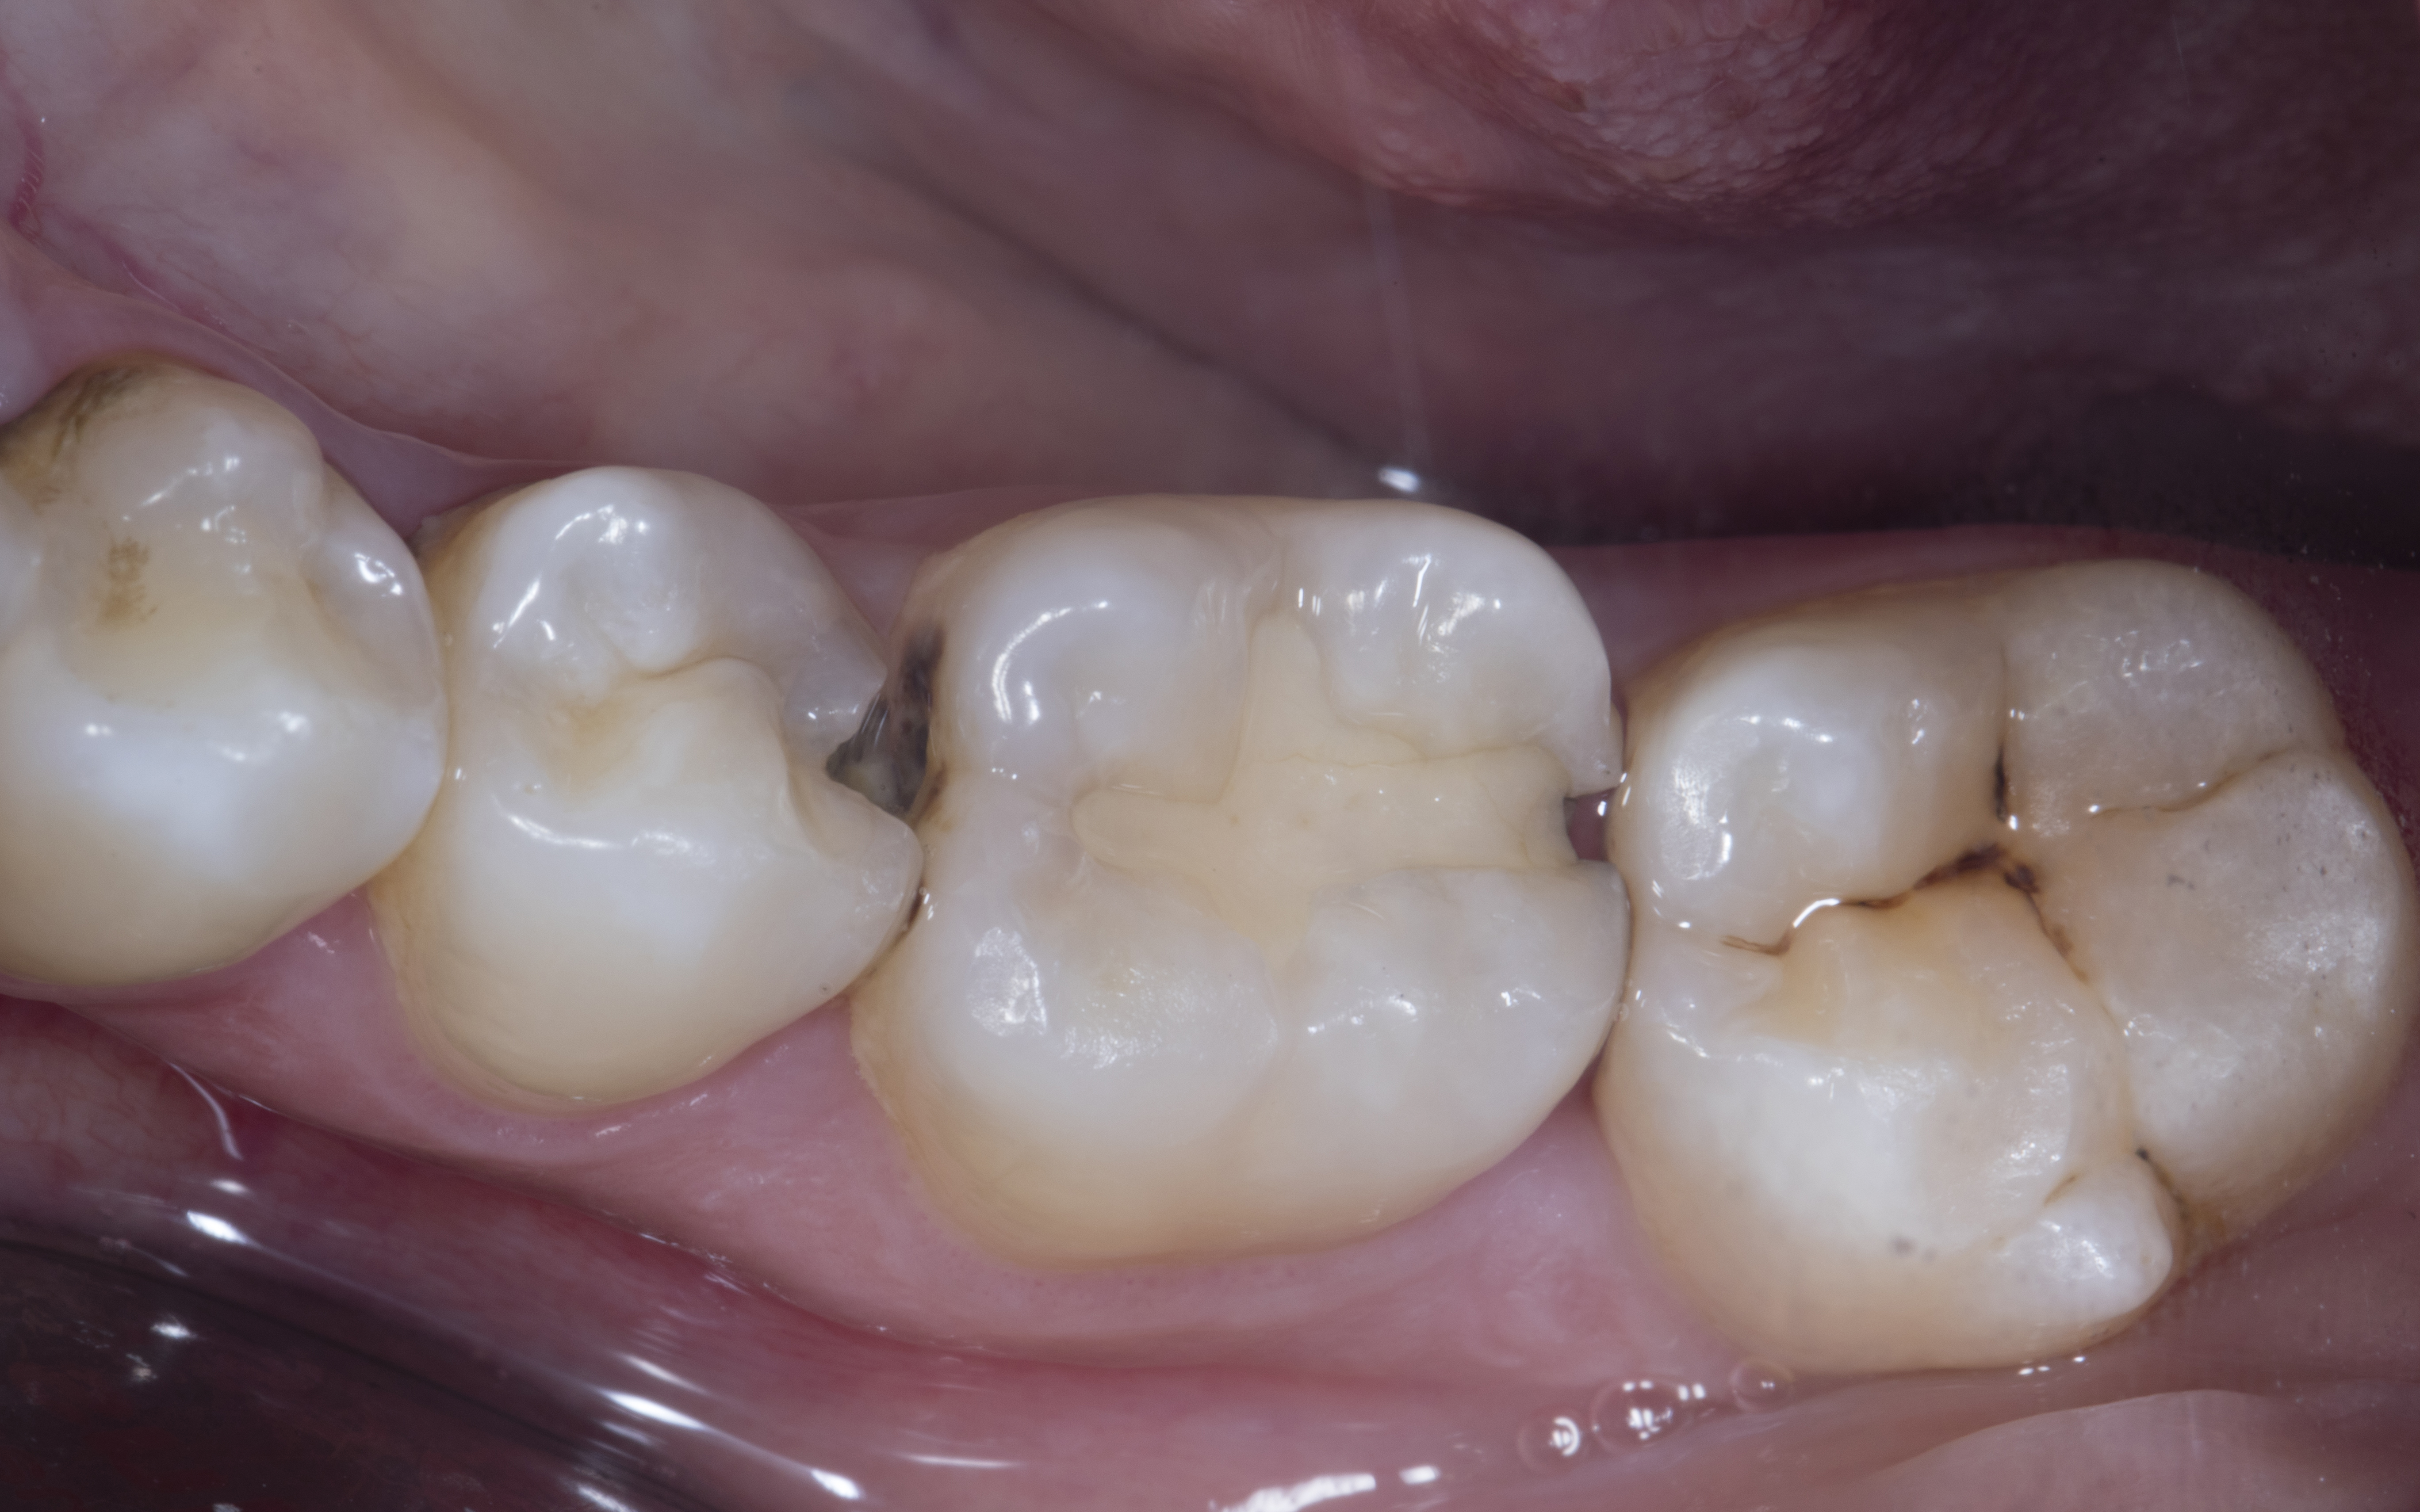

Figure 11

Figure 11. Rubber dam was removed and occlusion checked with 40 micron articulating paper in static occlusion.

Step 12 - Finishing and polishing was done using Shofu OneGloss, aluminium oxide impregnated silicone polisher.  A Super Buff disk was used after soaking in water for 20-30 seconds to achieve the final high gloss.

Figure 12

Figure 12. After finishing and polishing.